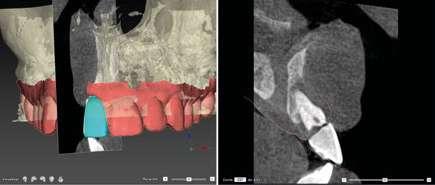

Para manejar todos estos datos vamos a necesitar de un software de diagnóstico y planificación digital como es el de DTX StudioTM Implant en el cual vamos a abrir tanto el CBCT como el escaneado intraoral y nos va a permitir fusionar ambas mayas utilizando la herramienta SMARTFUSION. En un caso como éste, donde tenemos un incisivo central, superior, derecho, fracturado que vamos a extraer debemos realizar previamente la extracción Virtual en el modelo digital para poder incorporarlo a la planificación de nuestro software.

Con todos estos datos fusionados en el DTX StudioTM Implant, lo que vamos a hacer es utilizar la función SMARTSETUP para tener un encerado Virtual que nos permita determinar la posición de la futura restauración del paciente, en función de la cual colocaremos nuestro implante y el aditamento más adecuado.

En este caso, podemos ver que tenemos un defecto óseo vestibular, se trata de un defecto de una sola pared de la zona a implantar. Intentamos planificar un implante inmediato y observamos la posibilidad de tener un buen anclaje apical por lo tanto nuestra primera opción va a ser la realización de un implante post extracción con regeneración de la pared vestibular mediate xenoinjerto óseo e injerto de tejido conectivo para mejorar el biotipo.

Lo realmente extraordinario de este software de diagnóstico y planificación es que en una sola imagen tenemos total control de la posición de nuestro implante y de nuestro pilar, en función del hueso de la encía y de la futura restauración. Por lo tanto vamos a realizar una implantología protética, y biológicamente guiada.